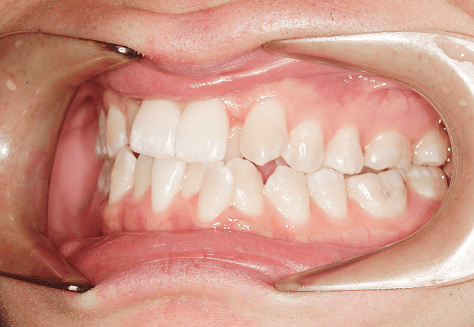

M.U

治療前

治療後

主訴

下の歯が特にガタガタなのが気になる。上の前歯が1本反対になっている。

診断

下顎前突・叢生・反対咬合

年齢/性別

20代/男性

抜歯部位

非抜歯

使用装置

上下インビザライン(PBM使用)

保定装置

ビベラリテーナー

料金

初回資料採得・・・・・・・30,000円

診断料・・・・・・・・・・33,000円

動的治療終了時資料採得・・5,500円 -

基本料金

950,000円

診察料金

5,500円×16回

治療期間

1年7カ月